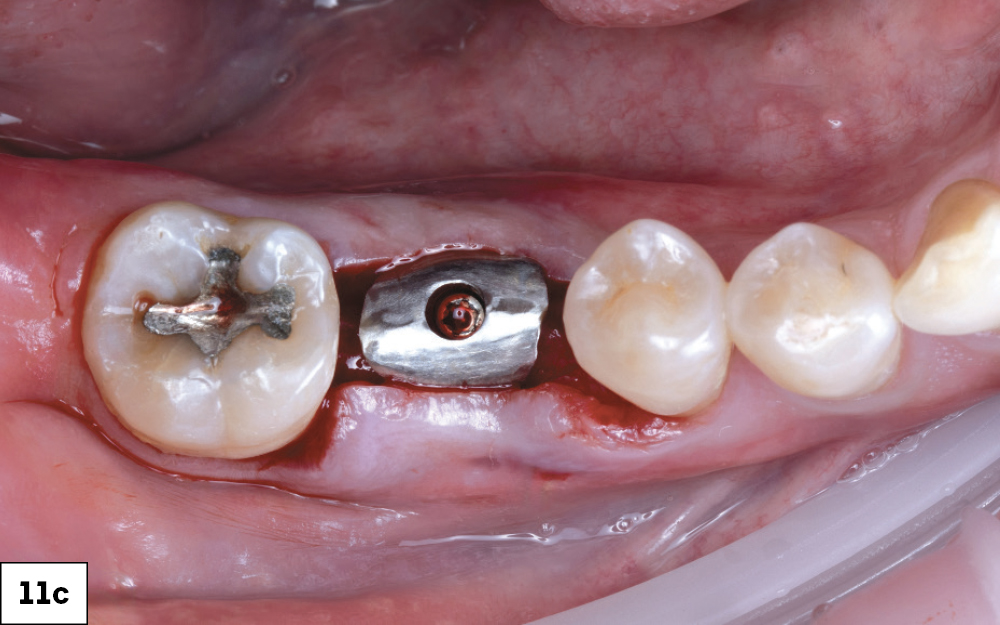

Implant Torqued to 35 Ncm

Glidewell Custom Healing Abutment Fully Seated

Figures 11a–11c: A 5 x 11.5 mm Glidewell HT Implant was placed into the fully prepared osteotomy. The implant was torqued to 35 Ncm. A Glidewell custom healing abutment was fully seated and the soft tissue approximated over the ridge. The custom healing abutment was chosen to guide gingival healing for an ideal esthetic outcome.